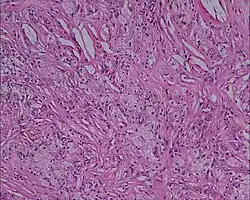

Histologie d'un xanthome, montrant des cellules avec de larges plages d'inclusions lipidiques, grossissement x 10, hématoxyline et éosine. Kumar et al. Cases Journal 2008

Histologie (Microscopie)

• Infiltrat dermique d'histiocytes géants parfois polynucléés (cellules de Touton) dont le cytoplasme spumeux est chargé de lipides : cholestérol essentiellement